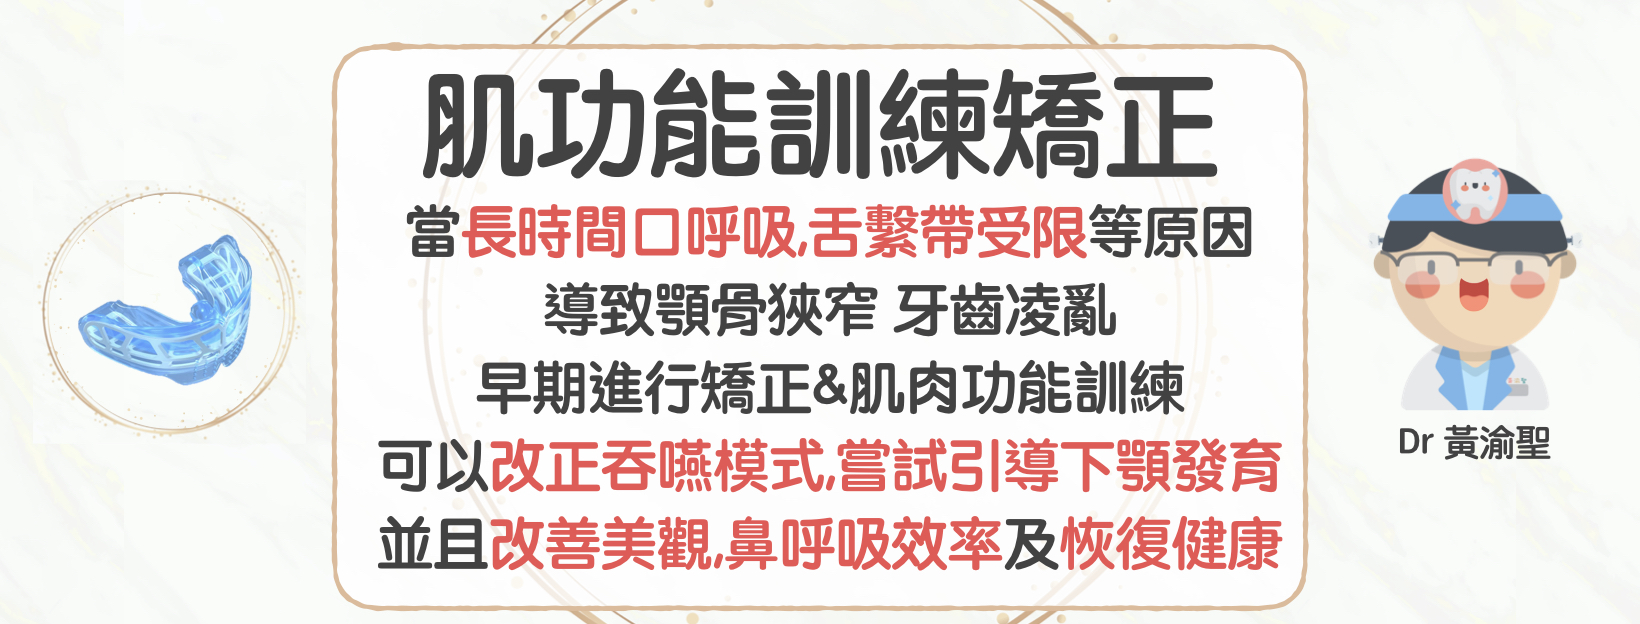

當長時間口呼吸,舌繫帶受限等原因

常因唇肌及舌頭力量不均勻

且長時間壓迫導致顎骨狹窄 牙齒凌亂

早期進行矯正&肌肉功能訓練

可以降低不良習癖對孩子生長造成負面影響

可以改正吞嚥模式,嘗試引導下顎發育

並且改善美觀,鼻呼吸效率及恢復健康

市面常見肌功能訓練治療裝置廠商為MRC及EF